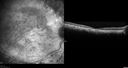

80 year old man Diagnosed at age 12 with retinitis pigmentosa. His central vision has been poor for a long time. He had surgery for nystagmus 3 times. He has worn glasses ever since he was 3 and he was bumping into walls when he was little. Night blindness was noticed by his mother at a young.

Mutations were confirmed in NR2E3 (Enhanced S Cone Syndrome)

VA OD HM; OS 6/200